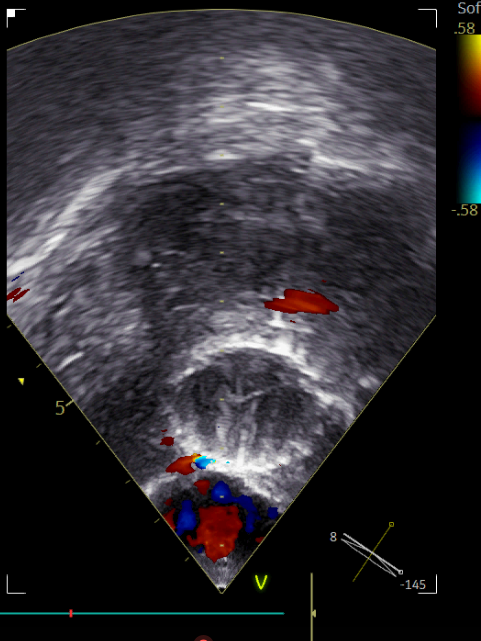

TEE显示主动脉瓣大量反流